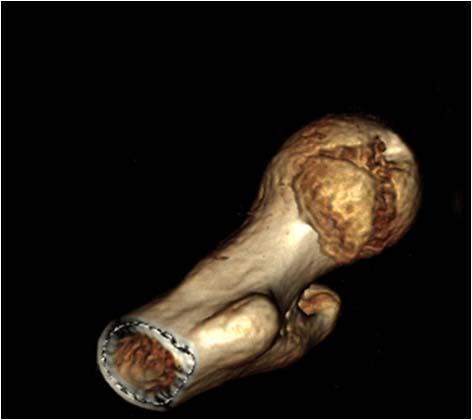

суставных щелей в сравнении с неповрежденной стороной. Сделали КТ,

которое подтвердило наличие внутрисуставного фрагмента задней стенки

вертлужной впадины и перелом нижне-медиального сегмента головки со

смещением (Pipkin IV).